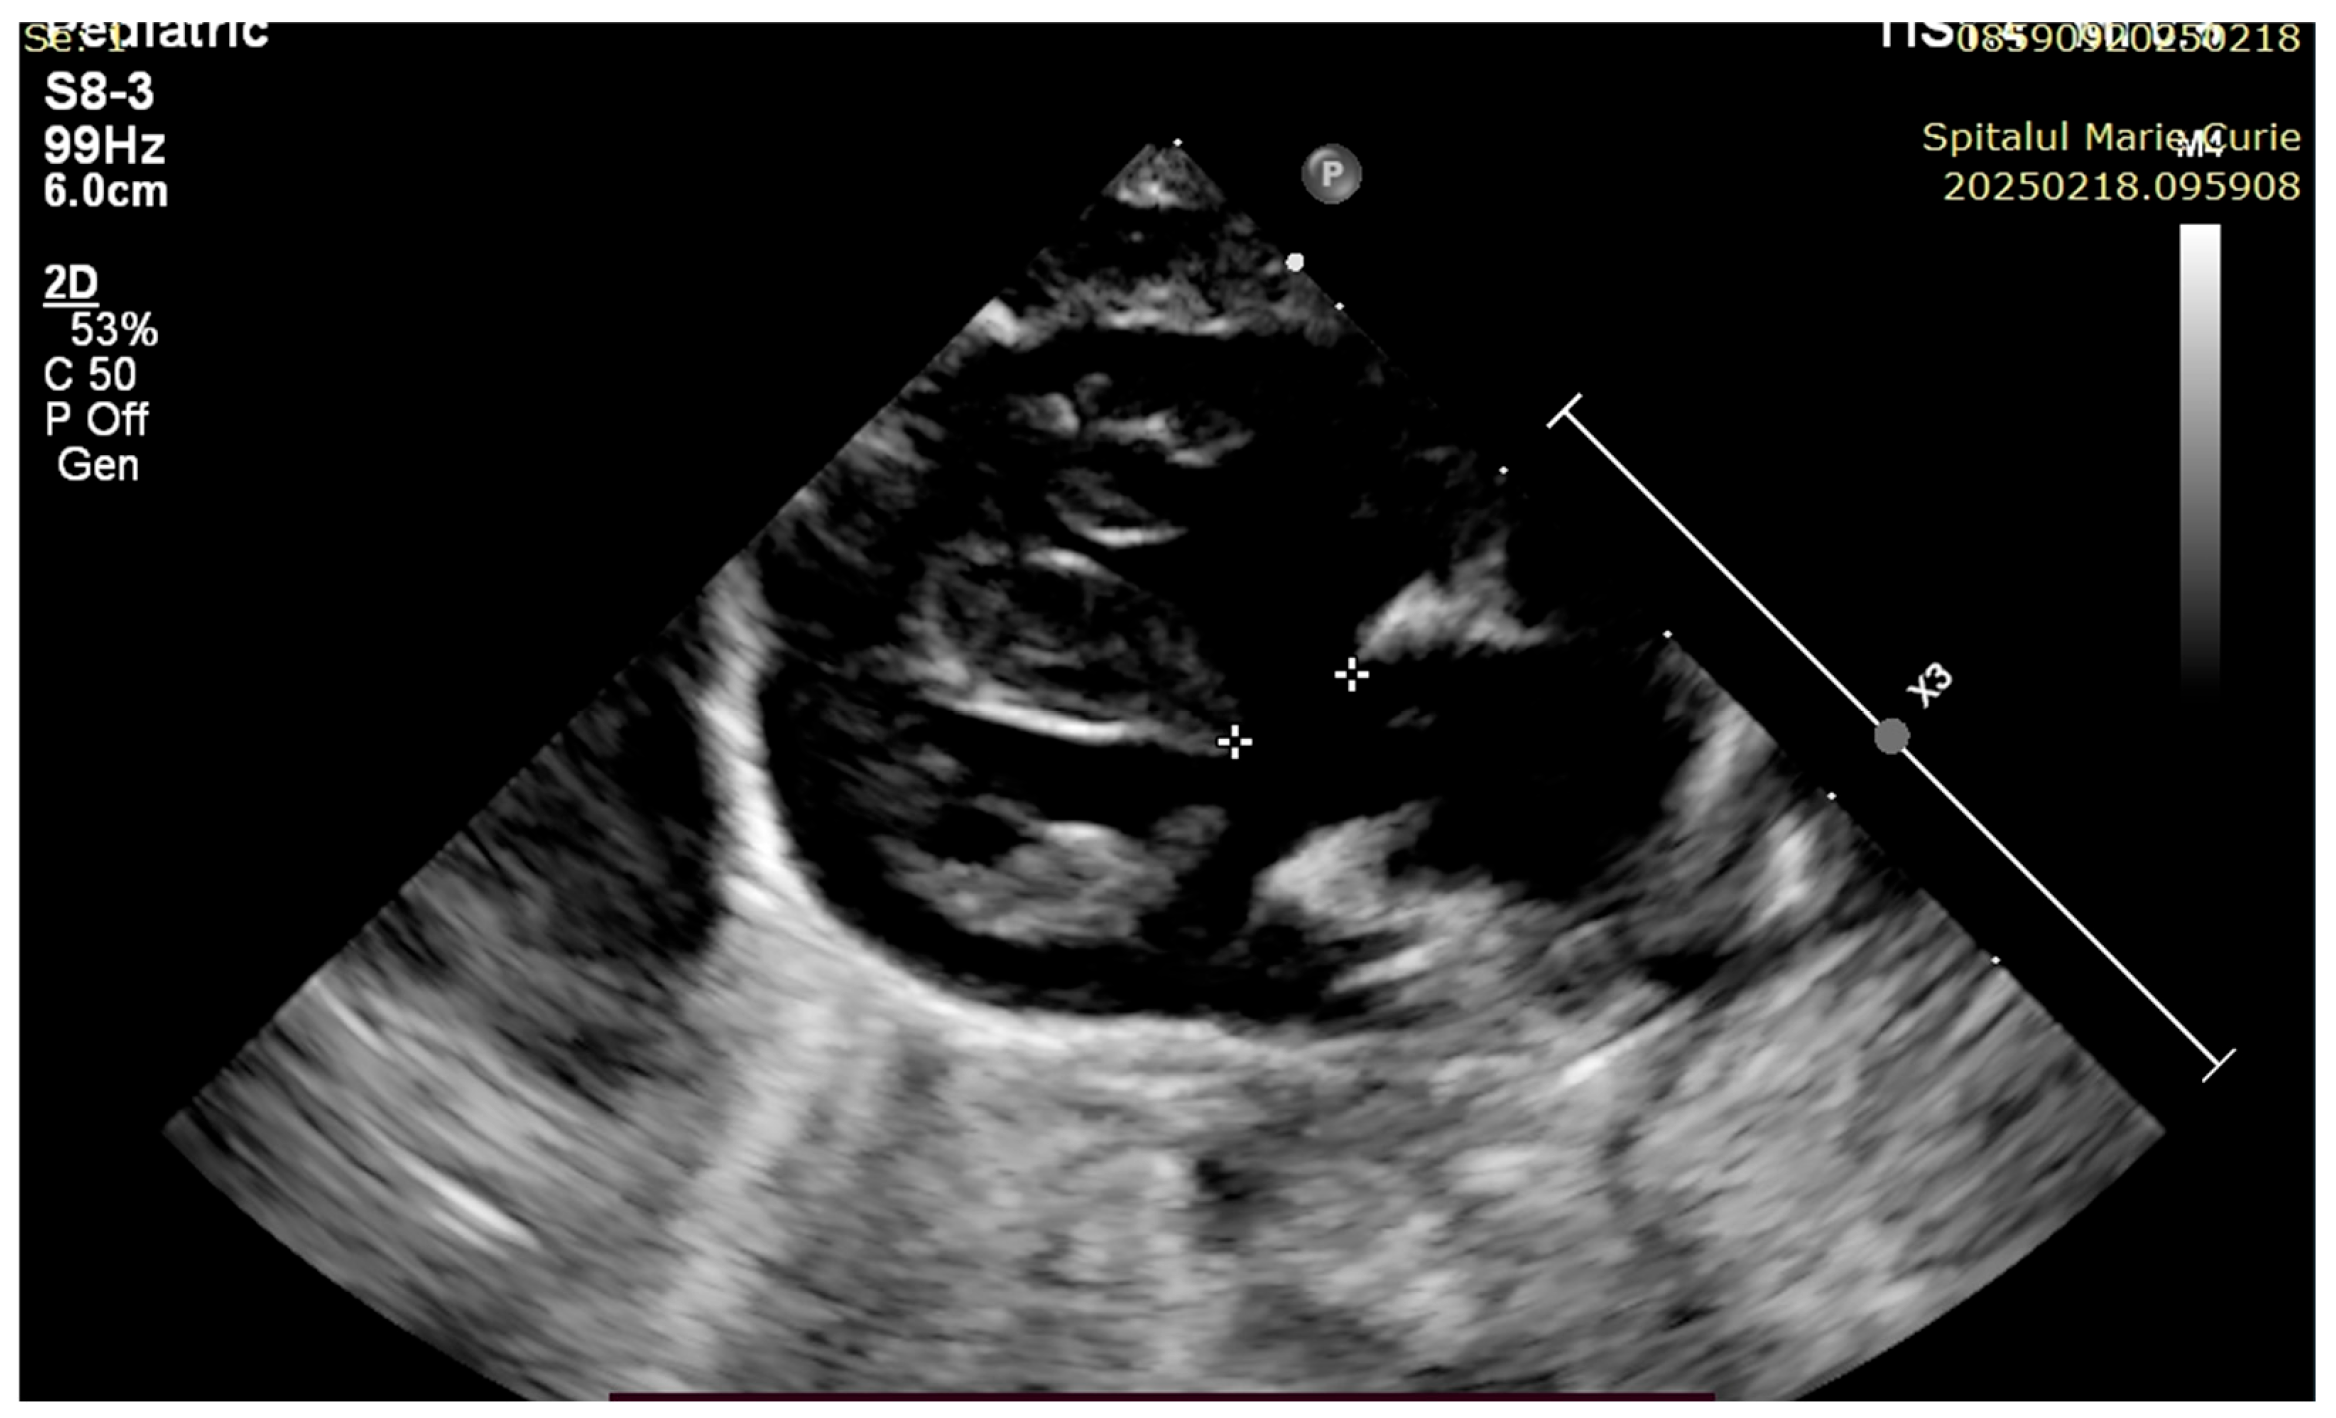

4. Case Reports